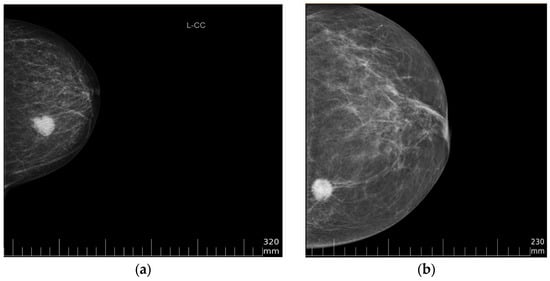

3.1. Datasets

| Type of data | DICOM files—full-field digital mammography craniocaudal (CC) and mediolateral oblique (MLO) images Excel file—age, pathological ground truth | DICOM files—full-field digital mammography craniocaudal (CC) and mediolateral oblique (MLO) images Excel file—age, pathological ground truth |

| Image resolution | 3518 × 2800 pixels | 2294 × 1914 pixels |

| Pixel spacing | 0.085 mm | 0.094 mm |

| Pixel depth | 12-bit (0–4095) | 8-bit (0–255) |